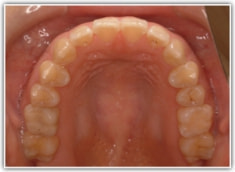

治療前

かなり重度のオープンバイト症例です。骨格的な要素も強く出ております。通常であれば外科矯正適応のパターンですが、当院では矯正治療のみで、外科は行いません。